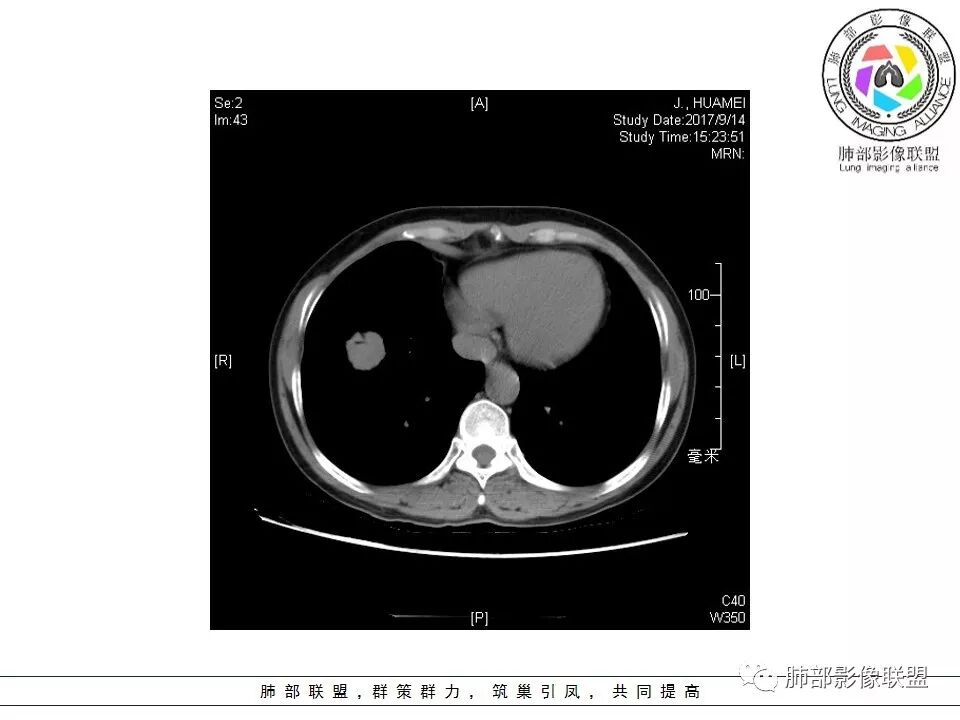

患者中年女性,因“体检发现右下肺占位4天。”入院,肿瘤标记物NSE轻高。

胸CT:右肺下叶前基底段占位性病变,内可见支气管穿过,病灶边缘不规则,呈浅分叶,未见明显毛刺。纵隔窗可见病灶密度相对均匀,增强可见病灶强化,内可见血管增粗,边缘模糊,总体考虑恶性,腺?。良性疾病鉴别错构。

南边老师分析

这个病灶边缘还是有一点点恶性征象,有分叶,似乎有点地方还有一些小毛刺样感觉

部分区域整体以膨隆为主,部分区域稍收缩

内部支气管走形非常自然,达远端稍扩张;内部血管穿行也非常自然

内部密度比较均匀,我们一般来说,首先良性肿瘤不支持,因为它里面的血管走形太自然了;然后就是炎性病变跟恶性肿瘤,但是它的边缘膨隆比较厉害,有些地方还毛刺,不是很清楚,倾向一个恶性病变

恶性的血管穿行自然,包括支气管稍扩张,最常见还是淋巴瘤,它强化比较均匀;

粘液腺癌一般支气管扩张比较罕见,这个密度及强化太均匀,不是很符合,所以把淋巴瘤放前面,癌待排;

方向定在恶性的,炎性病变不是很符合